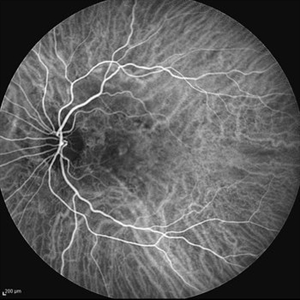

Behcet's Disease Behcet's DiseaseMar 13 2013 by Hamid Ahmadieh, MD Early phase FA of the right eye of a 23-year-old man with retinal vasculitis and branch retinal vein occlusion (BRVO) due to Behcet's disease . Photographer: Solmaz Shahmohammad, Negah Eye Center, Tehran Imaging device: Heidelberg Spectralis Condition/keywords: branch retinal vein occlusion (BRVO), retinal vasculitis